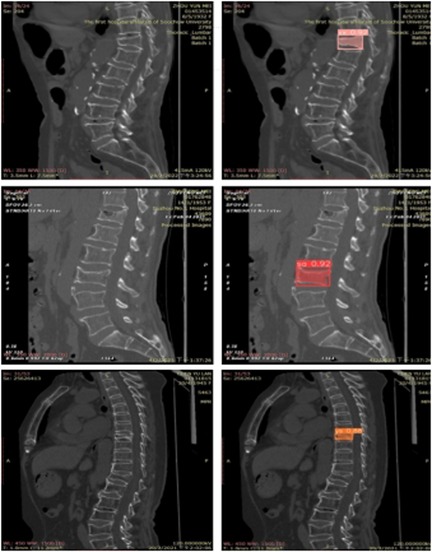

For clarity in the labeling process, this study adopts specific nomenclature: “ys” for crush fractures, “xx” for wedge fractures, and “sa” for biconcave fractures. This nomenclature is consistently used in the figures.

Extensive experiments were conducted on multiple spinal computed tomography (CT) images to validate the performance of the YOLOv8 algorithm. Figure 6 illustrates some of the detection results. In this figure, regions identified as wedge fractures and biconcave fractures by the YOLOv8 algorithm are highlighted, with corresponding confidence scores annotated. Specifically, the upper row of images in Figure 6 displays the detection of wedge fractures, labeled as “xx,” while the lower row of images shows the detection of biconcave fractures, labeled as “sa.” Both types of fractures are detected with a high confidence score of 0.92.